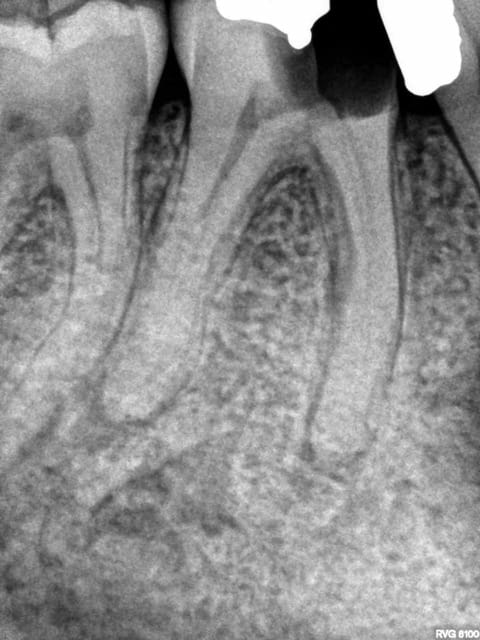

Pour l'instant je me contente de faire en sorte que les patients soient bien remboursés c'est pas forcément tout le temps l'indication clinique ( quoique ici ca l'était) mais ca va faire hurler les adeptes du no post no crown ( je me demande d'ailleurs comment il font pour faire accepter leurs devis avec notre nomenclature de merde).

Ici par exemple ic à 200 % ( mut ss 200 %) Et ceram à 400 %. Seul reste à charge 107,5 euros sur la molaire qui est remboursée à 300 % ( dents postérieures)

Les provisoires sont offertes -)))

Ca reste effectivement une dentisterie agricole.

une heure de rdv de a à z. Ca amortit la perte de temps des endos.

Les radios initiales quand meme. Pour les adeptes des soins conservateurs opposables. -))))

Pas la peine d'inventer de la prothèse elle est servie sur un plateau. -))))